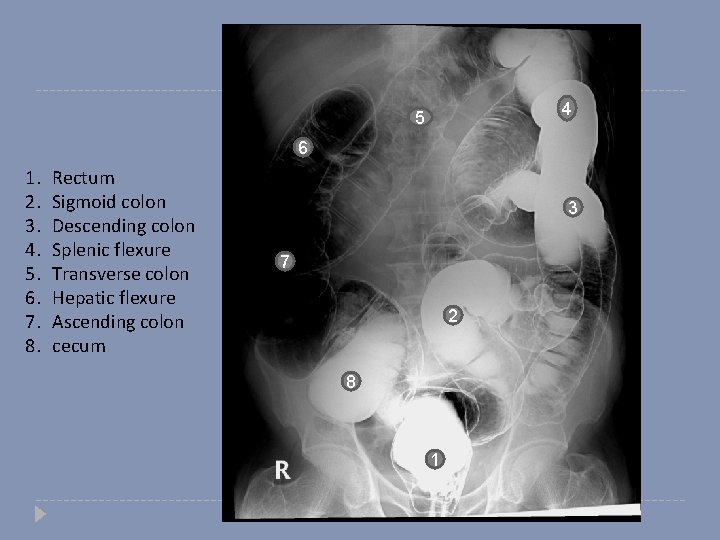

4 5 What type of this study? 6 Single or double? 3 7 2 8 1

4 5 6 1. 2. 3. 4. 5. 6. 7. 8. Rectum Sigmoid colon Descending colon Splenic flexure Transverse colon Hepatic flexure Ascending colon cecum 3 7 2 8 1